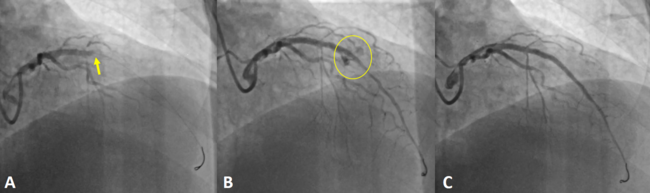

A 58-year-old man presented to the emergency department with chest pain consistent with angina. Electrocardiography revealed no ischemic changes; however, serial troponin measurements showed a rising trend. He was diagnosed with non-ST-elevation myocardial infarction and admitted to the coronary intensive care unit. Coronary angiography revealed a critical lesion in the left anterior descending artery (LAD), prompting immediate percutaneous coronary intervention (PCI) (Figure A). Following predilation, a 3.0 × 28-mm drug-eluting stent was deployed, and post-dilation was performed with a 3.5 × 15-mm noncompliant balloon. Shortly after, contrast injection revealed a no-reflow phenomenon in the LAD (Figure A, Video 1). Intracoronary adenosine and tirofiban were administered, with the patient remaining hemodynamically stable. Coronary flow was successfully restored. However, further imaging revealed an Ellis class III coronary perforation distal to the stent (Figure B, Video 2). Transthoracic echocardiography showed no pericardial effusion. Given the stable clinical status, a covered stent was successfully placed to seal the perforation (Figure C, Video 3). The patient remained asymptomatic during follow-up and was discharged with optimized medical therapy.

The no-reflow phenomenon remains one of the most challenging complications during PCI. It is defined as reduced coronary flow in the absence of mechanical obstruction, typically due to microvascular dysfunction, distal embolization, or reperfusion injury. Standard pharmacologic agents such as intracoronary adenosine, nitroprusside, calcium channel blockers, and glycoprotein IIb/IIIa inhibitors are recommended to restore microvascular flow. Importantly, persistent no-reflow can mask underlying mechanical complications such as coronary perforation. In this case, successful restoration of flow allowed identification and management of a life-threatening perforation. Clinicians should be cautious in interpreting no-reflow and should aim to re-establish flow to avoid missing critical complications.